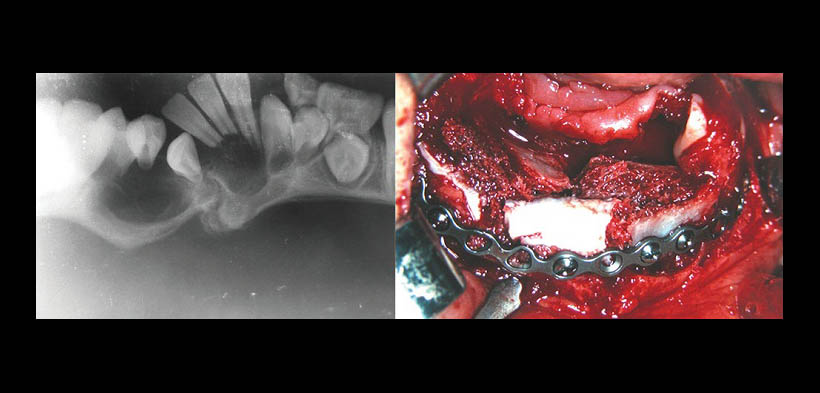

Fig. 1. Situación clínica preoperatoria de una paciente niña de 9 años con diagnóstico de GCCG.

Fig. 2. Radiografía panorámica preoperatoria del caso anterior, que muestra le lesión osteolítica bien delimitada. La imagen adyacente muestra el procedimiento quirúrgico, en la que se evidencia la colocación de placas de titanio para la fijación mandibular.